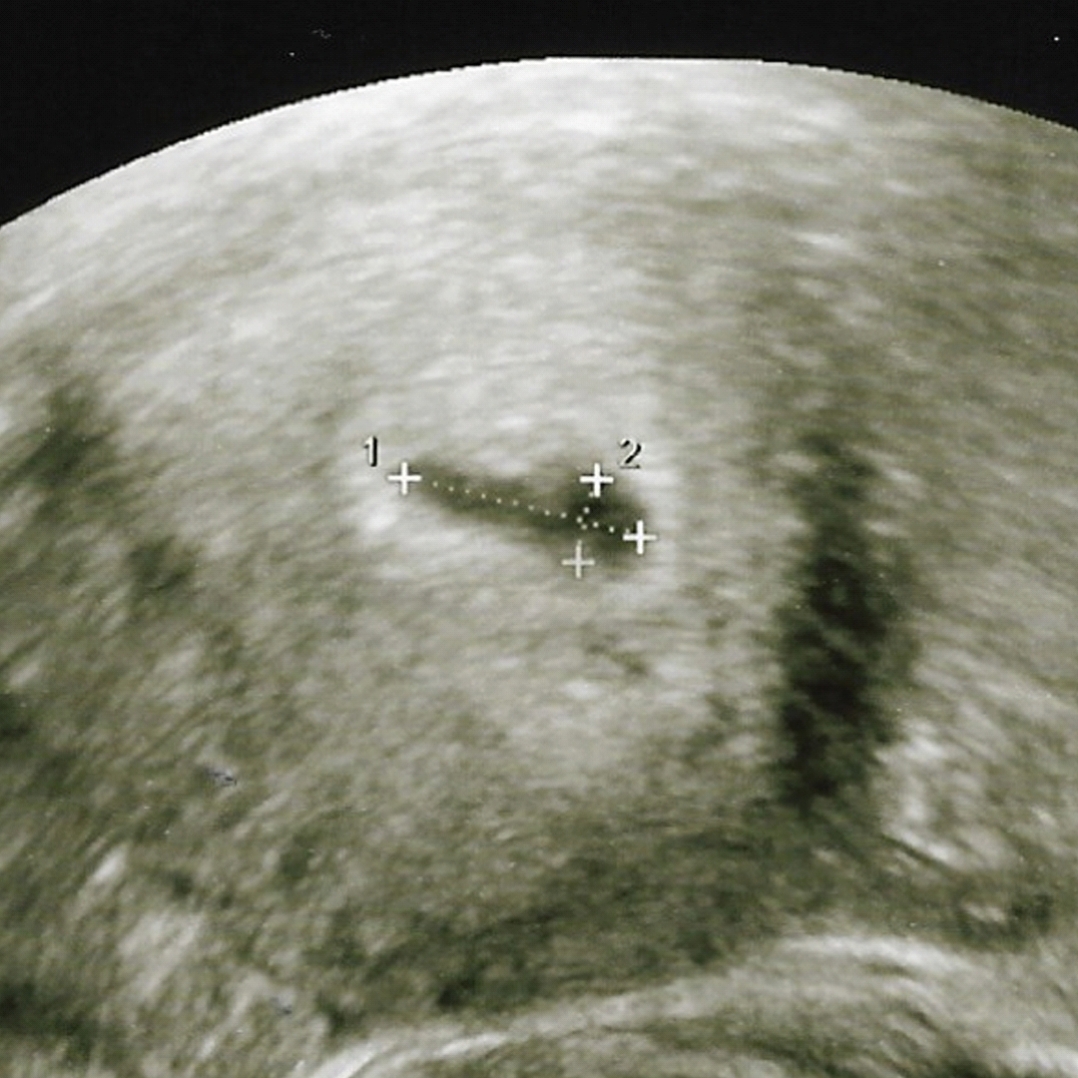

ภรรยาตั้งครนภ์ 5 week ไปซาว หมอบอกถุงครรภ์รีตอนนี้เครียดมากครับ

หมอแจ้งว่าถุงรีแบบนี้มีโอกาสท้องลม และทำหน้าเครียด ภรรยาเลยเครียดมากไม่เป็นอันทำอะไร

ปลอบยังไงก็ไม่หาย ช่วยแนะนำทีครับ

ใครเคยมีประสบการณ์บ้างครับ